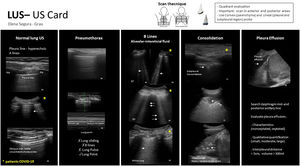

La ecografía pulmonar está siendo una herramienta de primera línea en el diagnóstico y seguimiento de los pacientes con COVID-19. Debido a la mayor utilización de la ultrasonografía pulmonar por profesionales con menos experiencia, elaboramos una guía básica en la que describimos de forma simple y resumida las áreas de exploración y las imágenes más frecuentemente encontradas en la ecografía pulmonar.

Por otro lado, están descritos los hallazgos ecográficos más típicos en los pacientes COVID-19, siguiendo los artículos encontrados hasta el momento en la literatura (figs. 1-4).